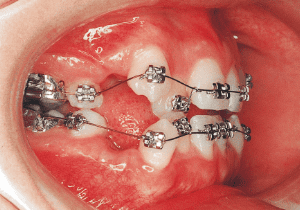

8 Beginning of 1st Phase 8-22-’88 7 years 1 month

The Edgewise appliance was applied locally (8) and removed after 11 months (9). However, as the maxillary molar region gradually became crossbite, the maxillary arch was laterally expanded using a quad helix.